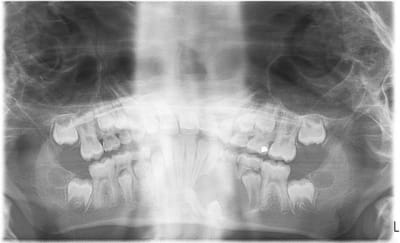

J'ai extrait la 74.

Elle était vivante, saine autant que je puissen en juger. Un surface osseuse nette et en bonne état était présente sous la dent.

A l'ouverture, la paroi kystique était épaisse et peu adhérente. Je n'ai pas pris le risque de tirer dessus, je l'ai vidé gentillement et suturé surtout pour limiter l'alimentation alimentaire de la cavité.

Ah j'oubliais! en curetant en périphérie de la 74 pas de sensation de racine de 73 et 75 proéminente...